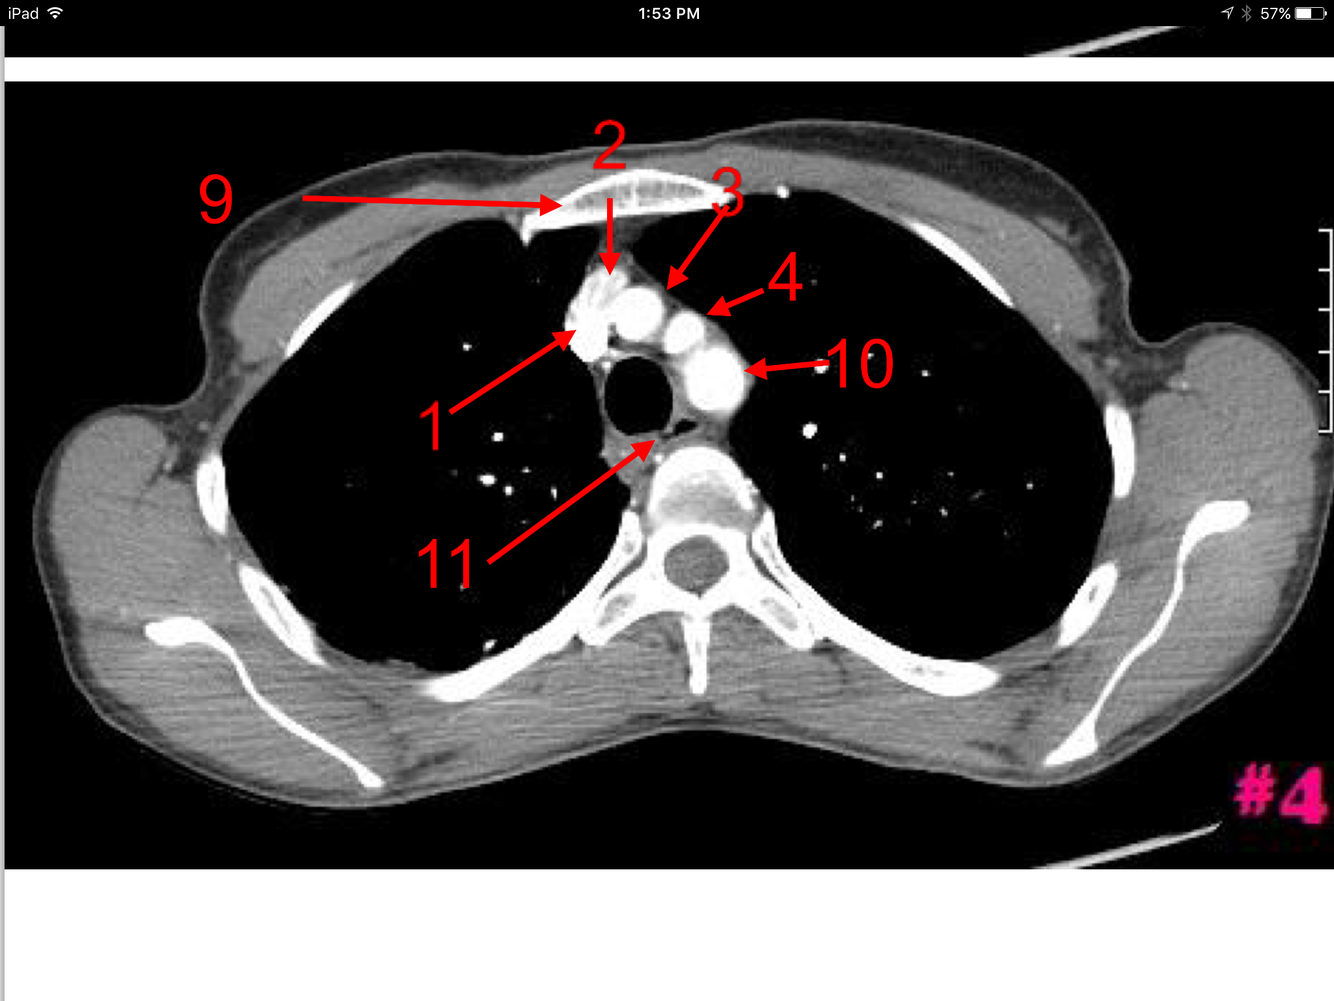

1

Q

A

Superior Vena Cava

Arch of the Aorta

Trachea

Body of the Rt scapula

Spinal cord

Body of the sternum